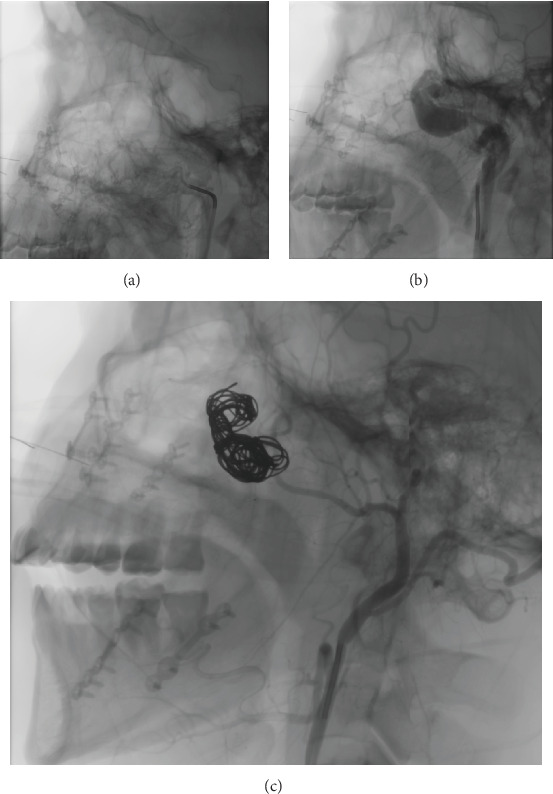

Arteriovenous fistulas rarely occur in the head and neck region. They typically arise from blunt or penetrating trauma but can develop as an uncommon complication following bimaxillary orthognathic surgery, a procedure to correct jaw deformities. This report describes a male patient who experienced an arteriovenous fistula after orthognathic surgery. We detail the diagnosis through patient symptoms and imaging, along with successful treatment via endovascular embolization. We also follow the patient for 1 year. This case highlights the importance of recognizing this rare complication to ensure prompt diagnosis and intervention. We discuss key points for preventing, diagnosing, and effectively treating arteriovenous fistulas after orthognathic surgery.